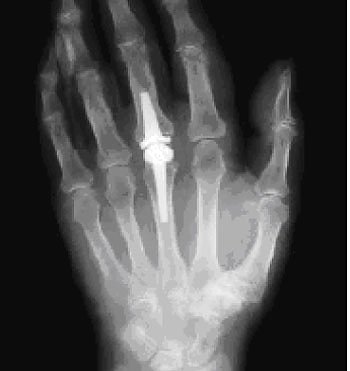

Röntgenaufnahme (Foto: Klinik Bleicherode)

Dass in Bleicherode große Gelenke wie Hüfte und Knie durch Prothesen ersetzt werden – und das in recht großer Anzahl – ist in der Region allgemein bekannt. Aber auch für andere Gelenke gibt es die Möglichkeit des Gelenkersatzes, wenn die nichtoperative Behandlung ausgereizt ist.

So auch bei Herrn E., der sich mit Beschwerden in einem Fingergrundgelenk in der Rheumasprechstunde der Klinik vorstellte. Alle nichtoperativen Möglichkeiten waren bereits ausgeschöpft, sodass für ihn eine andere Behandlung gefunden werden musste: Im März 2011 ersetzten die Bleicheröder Ärzte daher das Fingergrundgelenk durch ein Kunstgelenk aus Pyrocarbon.

Natürlich ist es mit der Operation alleine nicht getan, erklärt Oberärztin Anke Druschke, Expertin für Rheumaorthopädie der Klinik. Um langfristig ein optimales Operationsergebnis und eine gute Funktion der Hand im Alltag zu erzielen, ist vielmehr eine individuelle Nachbehandlung gemeinsam mit Orthopädietechnikern und Ergotherapeuten erforderlich. Auch darum

kümmern wir uns in der Klinik in Bleicherode.